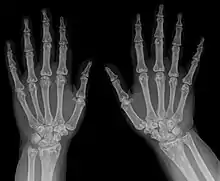

| Osteopoikilosis results in multiple enostoses. | |

An enostosis is a small area of compact bone within the cancellous bone.[1][2] They are commonly seen as an incidental finding on radiographs or CT scans. They are typically very small and do not cause any symptoms.[3] Their radiodensity is generally similar to cortical bone.[4] No treatment is necessary. Multiple enostoses are present in osteopoikilosis.[5]